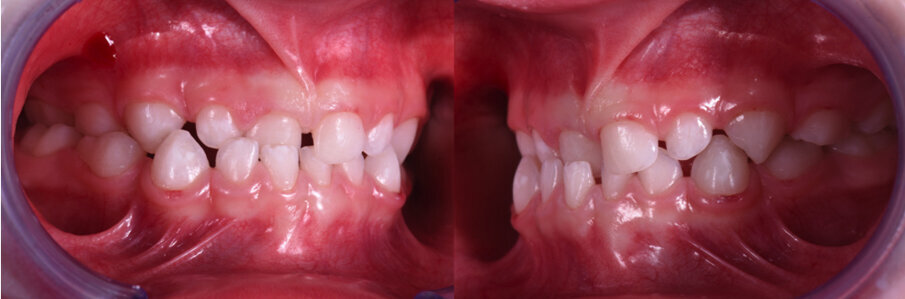

Caso 2 Paziente di anni 4, malocclusione dentale di III Classe, morso crociato monolaterale dx. La paziente viene trattata con dispositivo Amcop TC 2, il quale indossato tutte le notti e 1 ora di pomeriggio in 8 mesi risolve la malocclusione ripristinando il corretto rapporto occlusale; durante la terapia si riscontra un netto miglioramento della respirazione nasale e quindi il ripristino delle normali funzioni respiratorie. Il dispositivo, nei mesi successivi, viene indossato dalla paziente solo la notte per stabilizzare il caso e per guidare la crescita nel miglior modo possibile; all’età di 6 anni la paziente viene sottoposta a check-up ortodontico completo e quindi a panoramica e teleradiografia per poter analizzare anche la previsione di crescita e stabilire un eventuale step elastodontico (Figg. 15-23).